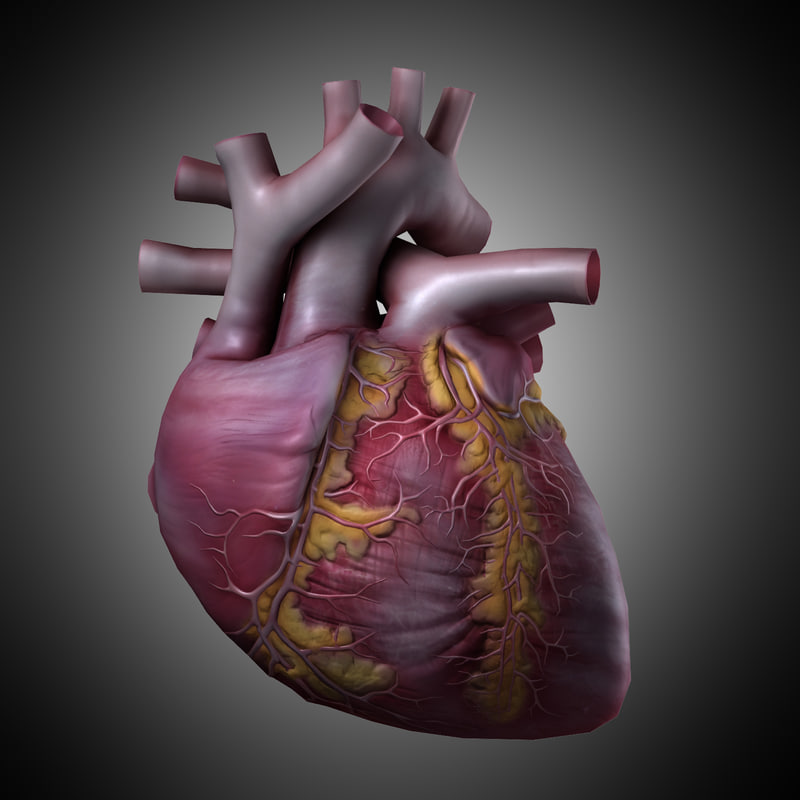

Human Heart Drawing Outline at GetDrawings | Free download  3d anatomy human heart

3d human heart  Animated Realistic Human Heart - Medically 3D asset

3D human heart anatomy model - TurboSquid 1283134  anatomy human heart 3d c4d

anatomy human heart 3d c4d  Modeled human heart section 3D model - TurboSquid 1657004

Heart by Rustamova on @DeviantArt | Anatomical heart art, Anatomy art, Heart drawing  3d human heart

3d human heart  Human Heart Pencil Drawing at GetDrawings | Free download

3d human heart  3d human heart

3d human heart  3d human heart anatomy model

3d human heart  Realistic detailed 3d human anatomy heart Vector Image

3D human heart model - TurboSquid 1149348  Get Easy Pencil Heart Art Easy Pencil Heart 3D Drawing Gif â Drawing 3D Easy

3d human heart  Human Heart Study Drawing, HD Png Download - kindpng

3d human heart  Royalty Free Human Heart Clip Art, Vector Images & Illustrations - iStock

3D human heart - TurboSquid 1737445  How to Draw a Human Heart - Really Easy Drawing Tutorial

human heart anatomy 3d max  Heart Anatomy Human Heart Images Hd 3D - Dreaming Arcadia

3d model heart anatomy  3d human heart anatomy model

3d human heart anatomy model  3d human heart section

3d Human Heart On Abstract Background Stock Illustration 635691020